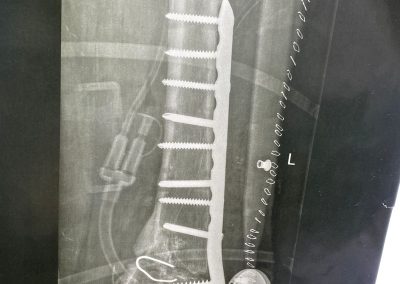

صورة اشعة تبين شريحة تم تركيبها بشكل خاطئ ترتب عليها اعوجاج بالركبة

الأشعات بعد الجراحة مباشرة و الاشعات الاخيره بعد الجراحة ب ٦ أشهر